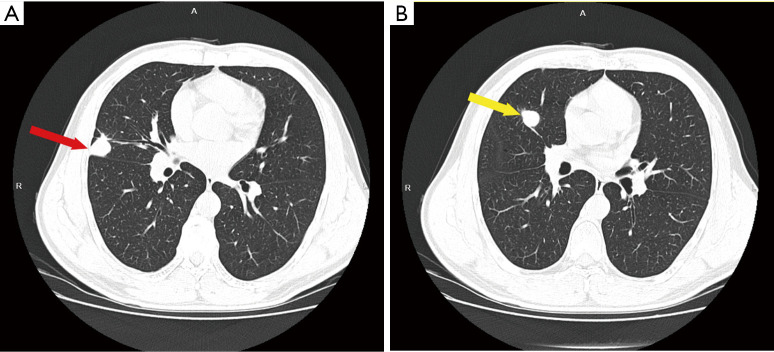

Case description: We report the case of a 49-year-old male who was diagnosed with stage IIIb (N2) lung adenocarcinoma. Next-generation sequencing revealed ROS1 fusions, and crizotinib was given simultaneously with targeted therapy during neoadjuvant chemotherapy. After 3 cycles of chemotherapy, surgery was performed, and the pathological results revealed major pathological response (MPR). Two years later, local and general examinations revealed no evidence of tumour recurrence.